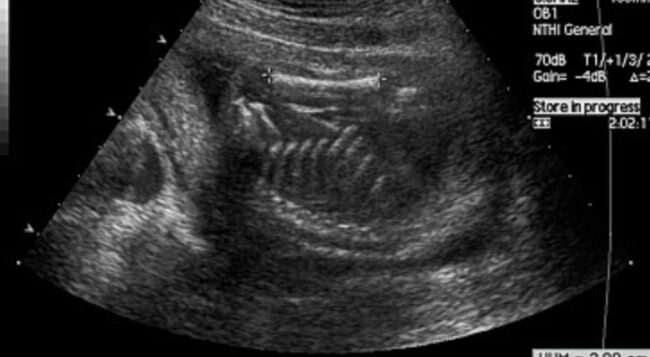

W poprzednich częściach cyklu dotyczącego ultrasonografii publikowanych na łamach „Inżyniera i Fizyka Medycznego” [1-5] przybliżono podstawowe pojęcia ultrasonografii i metody dopplerowskie. Ultrasonografia znajduje zastosowanie w wielu dziedzinach medycyny, w tym: okulistyce, ginekologii, neonatologii, położnictwie, internie, chirurgii, onkologii, ortopedii, dermatologii, kardiologii i innych. Pomiary w okulistyce Diagnostyka okulistyczna jest ściśle związana z badaniami USG gałki ocznej oraz oczodołu. Stosuje się głównie prezentacje…